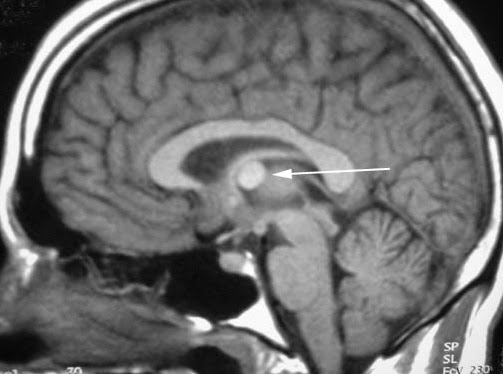

Pineal gland cyst treatment. The pineal gland is a small endocrine gland in the brain of animals with backbones. The pineal gland produces melatonin a serotonin derived hormone which modulates. A pineal cyst is a fluid filled mass that can occur in the pineal gland. True pineal gland cysts are not brain tumors.

Arachnoid cysts are found in the space between the two innermost layers of the coverings of the brain known as the meninges. Treatment may simply require watching the. Advanced treatment of pineal cysts. Pineal cysts are benign fluid filled deposits located in the pineal gland region of the brain.